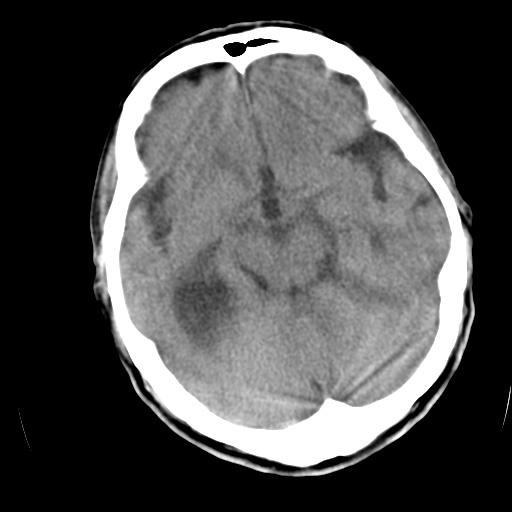

以下是引用泪洒红尘在2009-3-23 19:53:00的发言:[br]第四脑室以上脑室明显扩大,脑沟脑裂无明显增宽加深征象,符合交通性脑积水ct表现。

以下是引用xulianj在2009-3-23 20:31:00的发言:[br]右侧侧脑室扩大,中线结构左移,考虑梗阻性脑积水,建议mri检查。